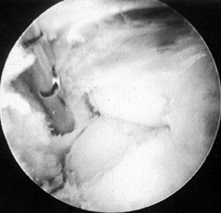

Bring in a shaver through the medial

portal. Keep the open side of the debrider pointing toward the humerus.

Release the anterior capsule and debride adhesions from the humerus. If

the capsule is thickened, direct the shaver anteriorly with caution and

debride this tissue (Fig. 82.18; see also COLOR FIG. 82.18).

Figure 82.18. (See COLOR FIG. 82.18) Arthroscopic view of arthrofibrosis in the anterior compartment. -